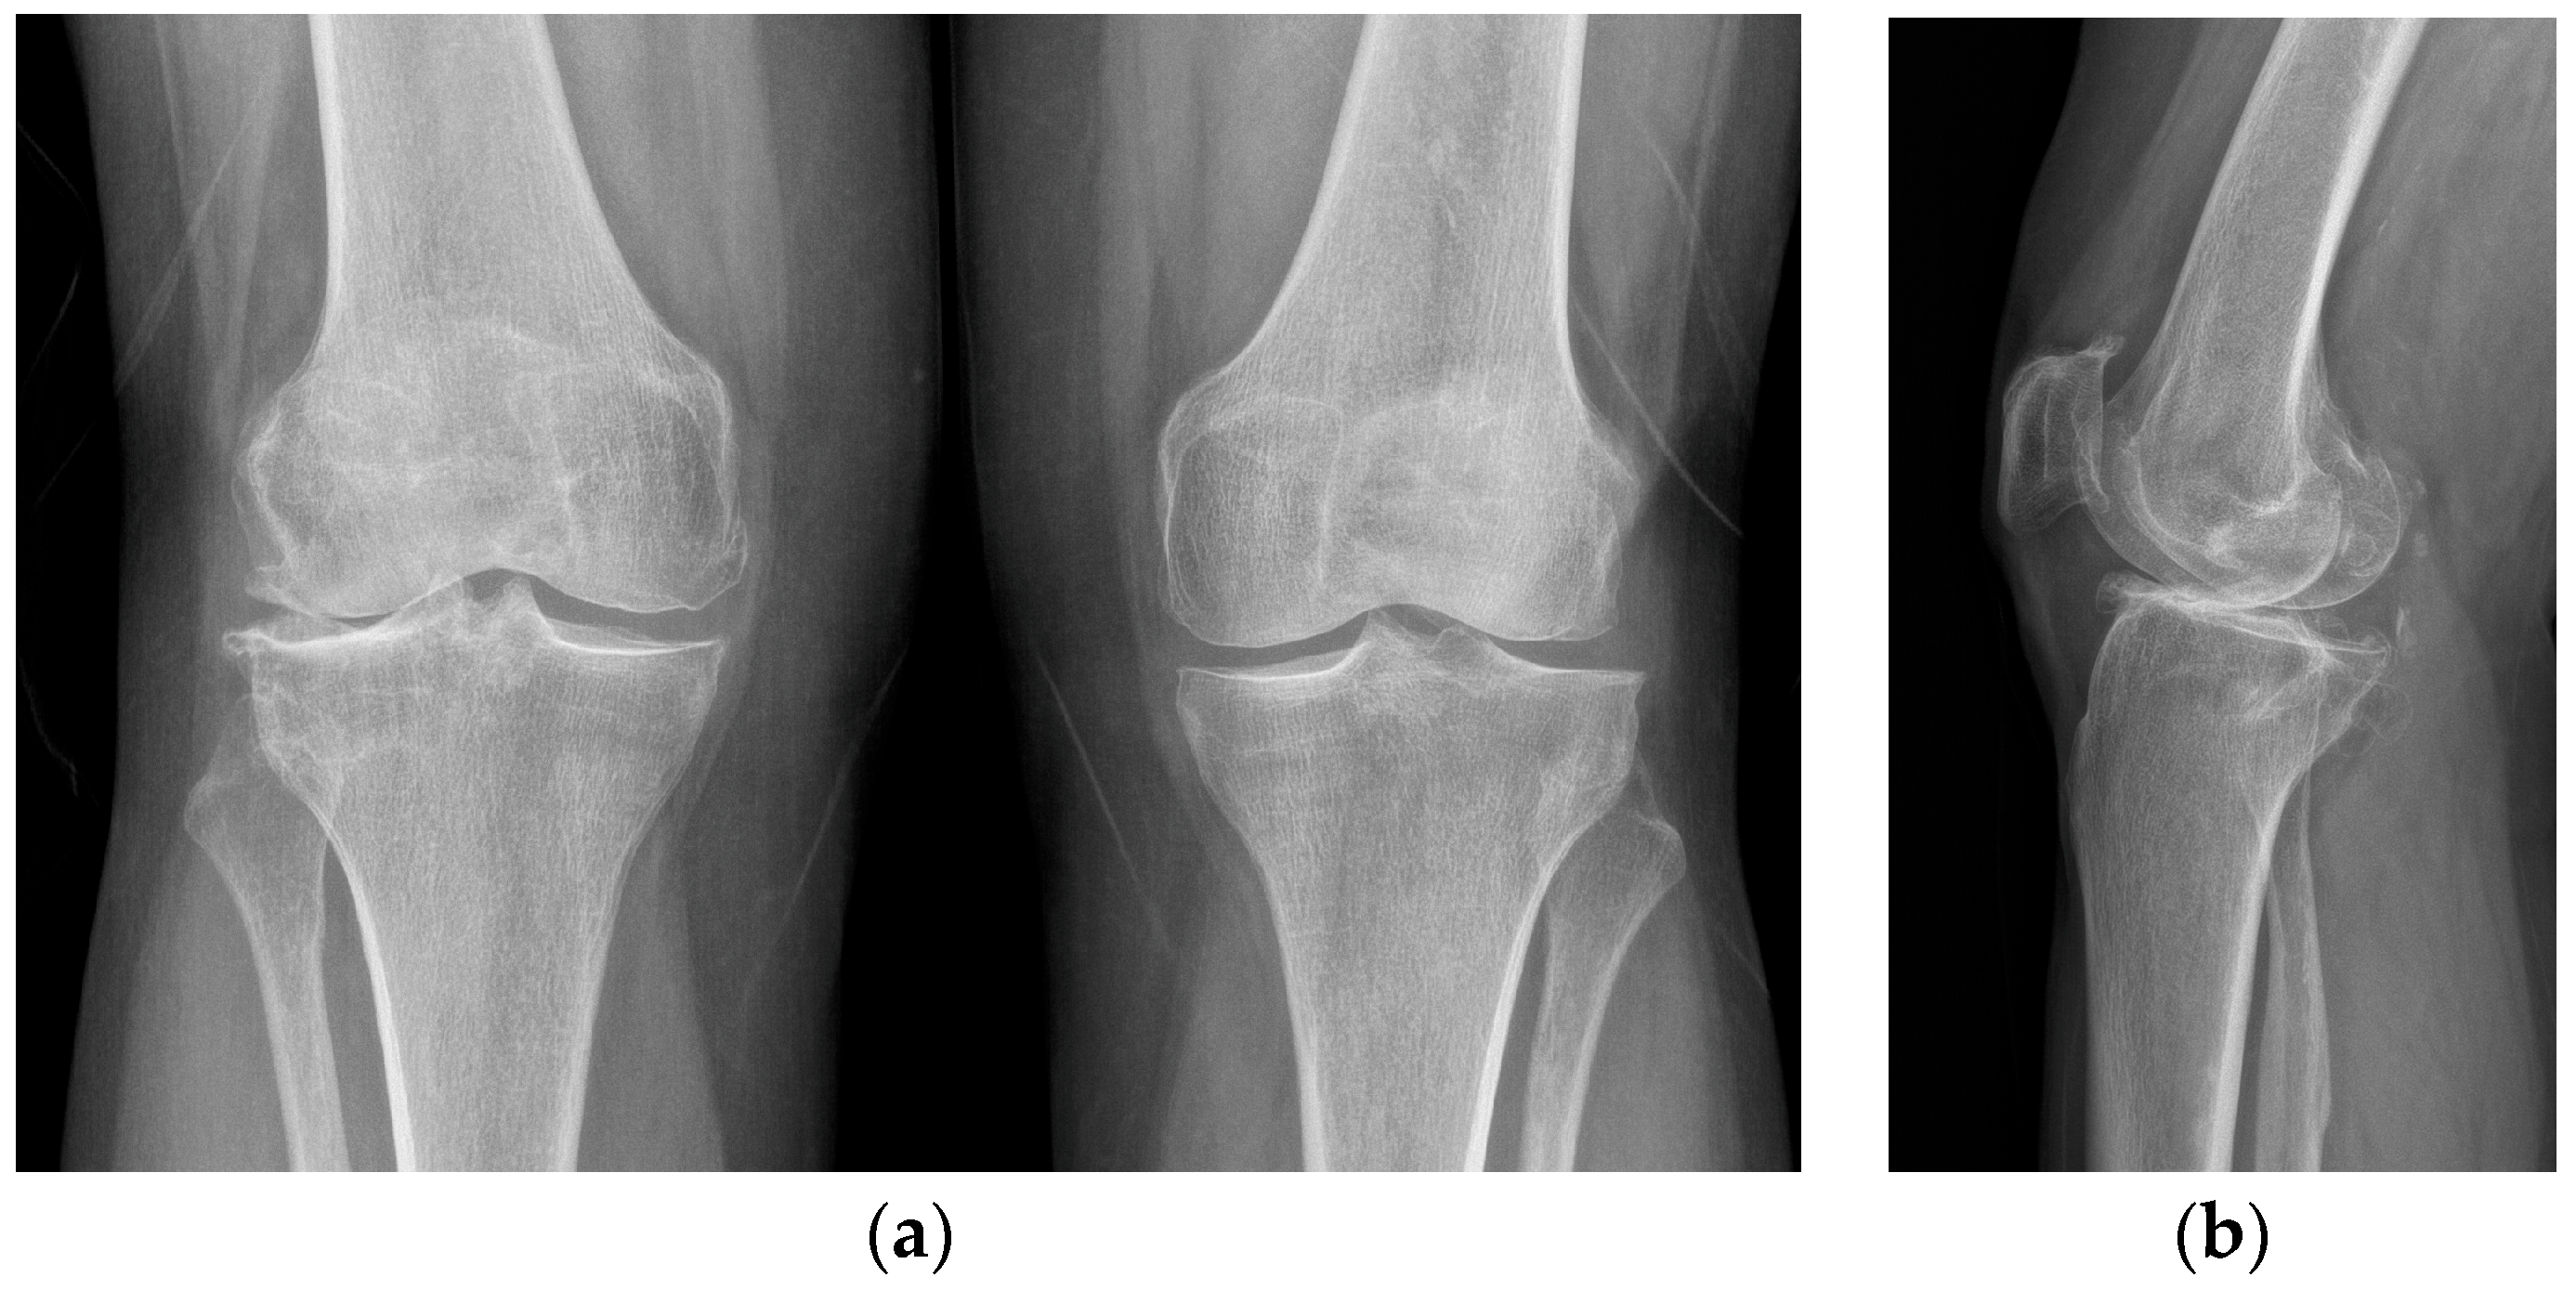

X-rays were obtained. The X-rays showed a valgus knee (4.8 degrees of mechanical axis and 11 degrees of anatomical one) (Figure 1). The antero-posterior X-rays showed lateral osteoarthritis. Based on Kellgren–Lawrence, there was evidence of grade IV on the lateral compartment and a grade II–III on the patella-femoral joint and on the femoro-tibial compartment (Figure 2).

Figure 2.

Pre-operative X-rays. (a) AP View: Kellgren–Lawrence grade IV on lateral compartment, grade II on medial compartment; (b) Lateral View: Kellgren–Lawrence grade III on patellofemoral joint.